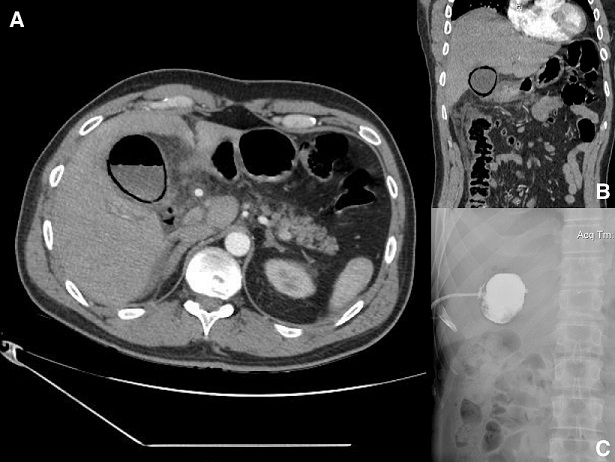

A 43-year-old, otherwise healthy, male patient presented at the emergency department, with a 3-day history of right upper quadrant abdominal pain and fever of 39°C. Physical examination revealed positive Murphy’s sign and jaundice. Laboratory values revealed leukocytosis (18,000/ml), elevated CRP and liver function tests (direct bilirubin, ALP, ³GT). Ultrasound scanning demonstrated distention of the gallbladder, with wall thickening, pericholecystic fluid and a gallstone impacted in cystic duct. The patient was empirically started on broad-spectrum antibiotics. An abdominal CT scan on the following day revealed gas in the gallbladder wall and lumen (A, B). A percutaneous cholecystostomy was placed (C) and his clinical condition improved dramatically over the following hours, with normalisation of inflammatory indices and liver chemistry. He is scheduled to undergo laparoscopic cholecystectomy in 8 weeks. Emphysematous cholecystitis usually begins as a typical case of acute cholecystitis, but ischemia and gangrene soon develop in the gallbladder wall, due to intramural translocation of gas-forming microorganisms (Clostridium, E. coli, Klebsiella, Streptococci). Predisposing factors include diabetes mellitus, immunosuppression, peripheral vascular disease, abdominal surgery and trauma. Initial assessment with ultrasound may show reverbation artifacts due to the presence of air. CT scans are considered more specific and sensitive, demonstrating a gaseous halo around the gallbladder as well as air within its lumen. Emphysematous cholecystitis is a surgical emergency. Early intervention with surgery or percutaneous cholecystostomy is the mainstay of therapy. Left untreated, it can progress to perforation, pericholecystic abscess or bile peritonitis. Mortality rate for uncomplicated emphysematous cholecystitis is 1.4%, whereas for complicated cases it can reach up to 25%.